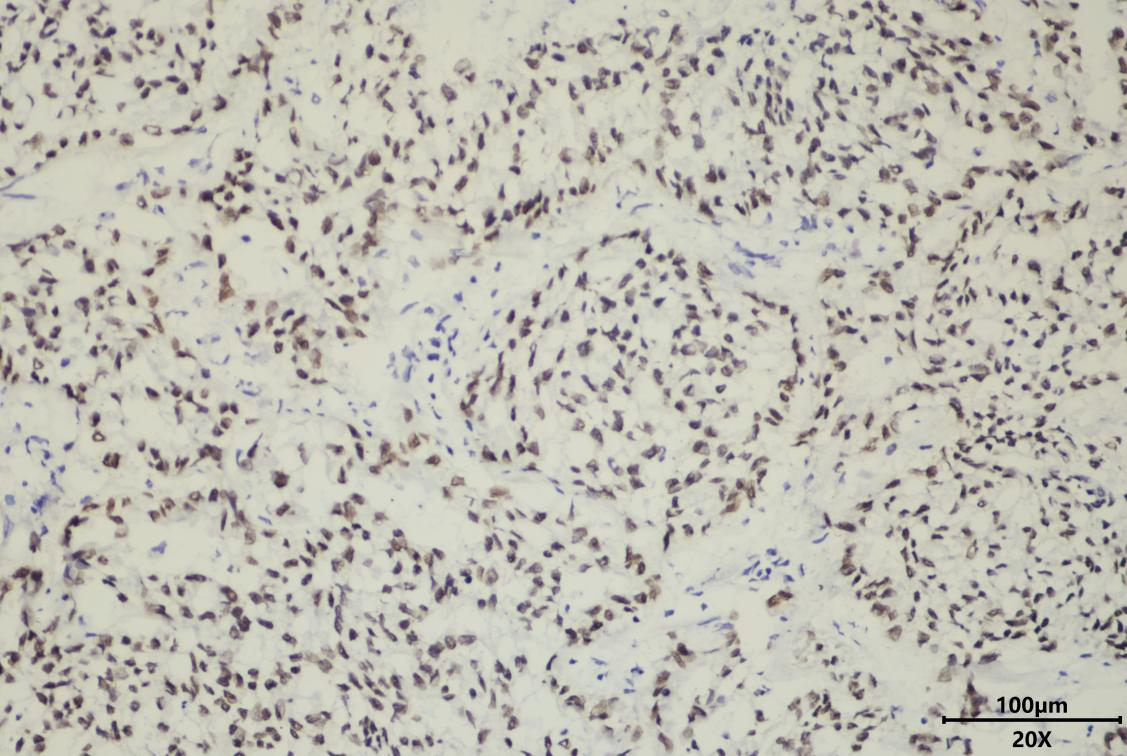

肺神经内分泌瘤术中冰冻CK免疫组化染色